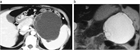

1. IPMNとは膵管内に乳頭状に発育し、多量の粘液を産生、膵管拡張を来す疾患である。主膵管型と分枝膵管型に分類され、主膵管型では主膵管のびまん性拡張像、分枝膵管型では分枝膵管の嚢胞状拡張像(ブドウの房状)が特徴である。

1. 壮年~高年男性の膵頭部に好発し、膵管との交通を認め、膵管内を進展し、随伴性膵炎を高率に合併する。